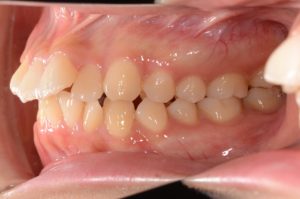

【スプリント治療前】

約4ヵ月間、就寝時にスプリント使用していただきました。

歯並びは変わっていませんが、顎の位置が正常に安定したことで

噛み合わせの位置が変化していることが分かります。